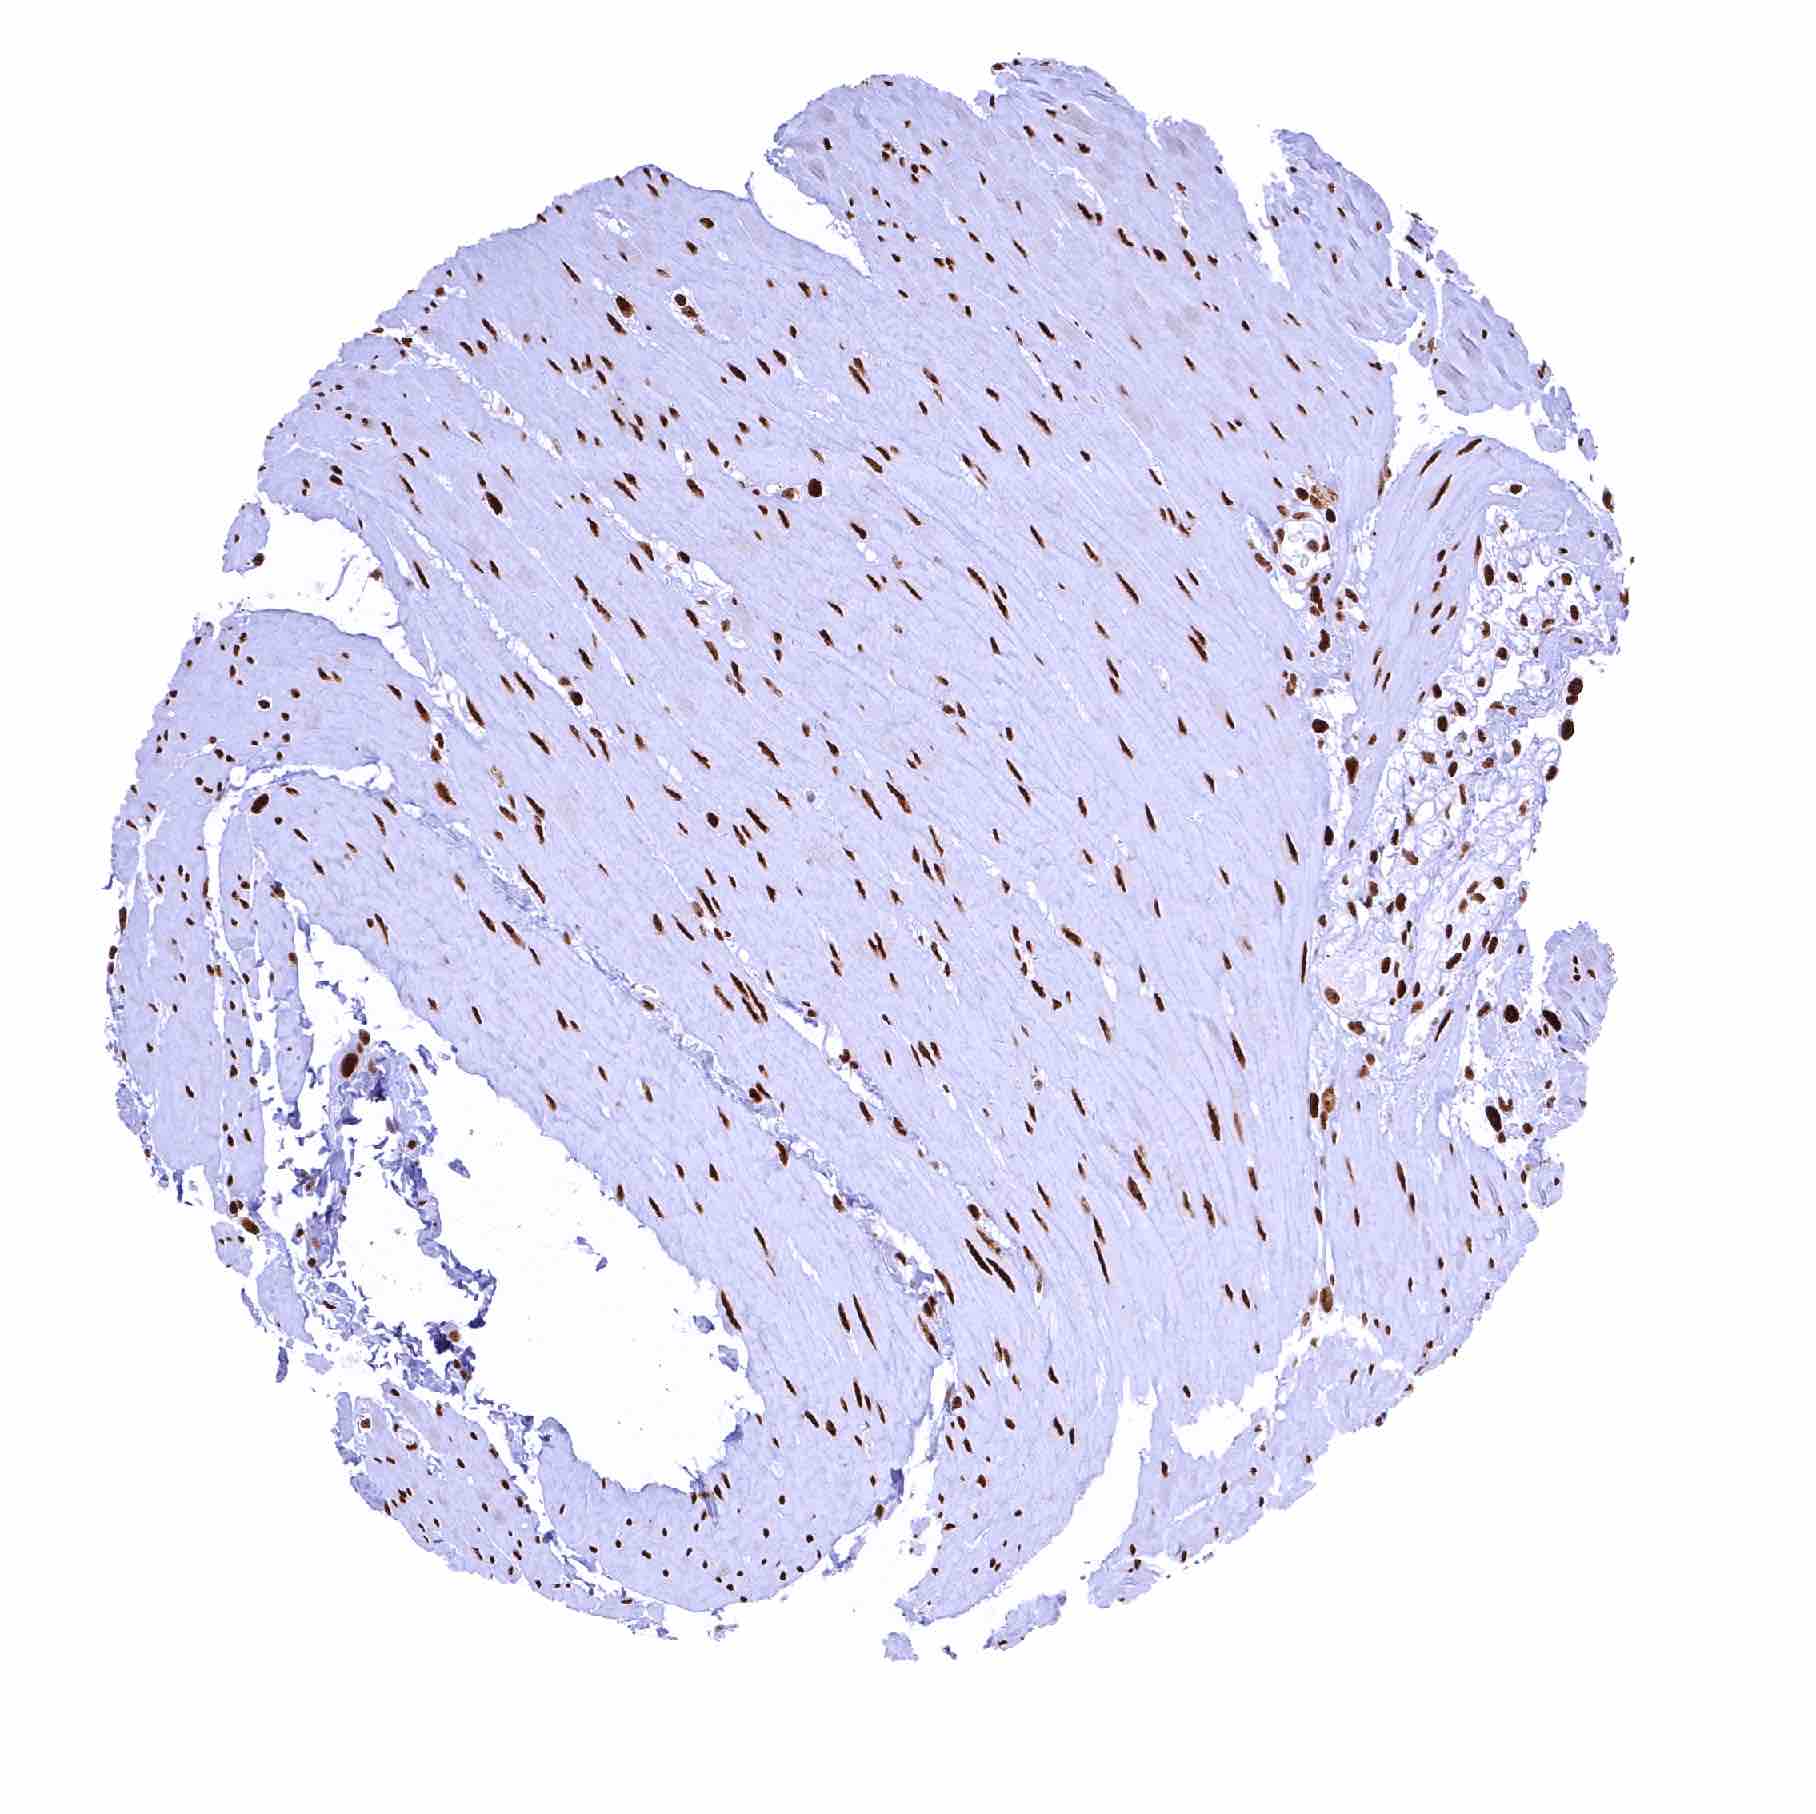

Heart muscle